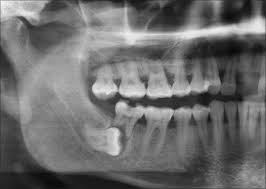

Gömülü 20 yaş dişleri 18 ila 22 yaş döneminde tam olarak sürmeye başlar. Genellikle çene yapılarının nesilden nesile daralma eğilimi göstermesi sonucunda çenede yer bulamayarak çeşitli şekillerde gömülü kalabilmektedir. Gömülü kalan 20 yaş dişleri hiç bir problem çıkarmadan senelerce durabildiği gibi öndeki dişlerde çapraşıklık, yan dişleri çürütme, çevre mukozal dokularda iltihabi durumlar gibi olumsuz sonuçlar yaratabilir. Bu olumsuz durumlar rutin panaromik röntgen ve muayenelerde teşhis edilebileceği gibi çeşitli semptomlar göstererek hastaların kliniğe başvurması sonucu da belirlenebilir.

Literatürde bu konuya çeşitli yaklaşımlar bulunmaktadır. Profilaktik gömülü diş operasyonu adı altında bütün 20 yaş dişlerinin çekilmesi gerektiğini savunan çalışmacılar bulunmaktadır. Ancak kar zarar dengesi açısından değerlendirildiğinde gömülü diş operasyonu sonrası bölgede daha fazla zarar ortaya çıkma ihtimali varsa, rutin kontrolleri sağlamak şartı ile takip edilmesi önerilmektedir. Ancak çeşitli sebeplerde derin çürükleri bulunan kanal tedavisinin mümkün olmadığı durumlarda ve ciddi diş eti iltihabına bağlı olarak ağrı ve rahatsızlık veren vakalarda her türlü risk alınarak çekim planlanır. Ortodontik tedavi öncesi tedaviyi planlayan hekim tedavi sonrası nüks riski görüyor ise gömülü dişlerin çekilmesini uygun görebilir. Özellikle alt 20 yaş dişleri horizontal olarak gömülü kaldığı durumda önündeki 7 numaralı ikinci büyük azı dişini çürütmeye başlar. Çürük başlangıcı farkedildiğinde çekim kararı verilmelidir ancak bazı durumlarda horizontal konumda olan gömülü diş ile 7 numara arasında mesafe gözlenirse takip kararı verilebilir.